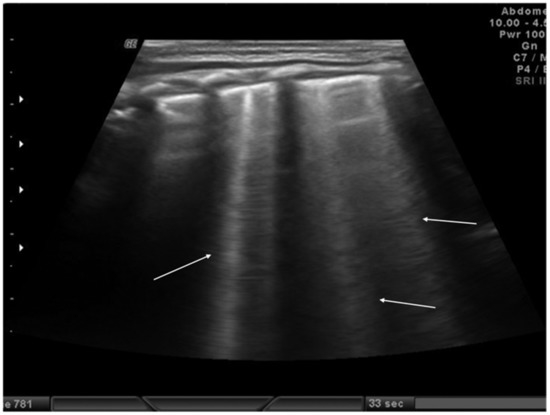

The role of LUS in identifying pleural effusion is also well established [53]. In fact, many studies have evaluated the efficacy of lung ultrasound in the diagnosis of pleural effusion, calculating its sensitivity and specificity, which have often been close to 100% [54]. These studies have confirmed the superiority of ultrasound over CXR in pleural effusion detection due to the capability of ultrasound to detect fluid collections as small as 20 mL [55]. Usually, pleural effusion can be visualized by ultrasound as a dark and anechogenic region located above the diaphragm that also determines the disappearance of the mirror image of the liver and spleen in the lung fields, which can be visualized in the healthy lung (Figure 10) [14]. Ultrasound also allows quantifying the amount of fluid accumulated in the pleural cavity well and characterizing the fluid collection differentiating a transudate from an exudate. The transudate is characterized by a dark image without internal echoes, representing an uncomplicated collection, while an image characterized by a septate or multiloculated corpuscular fluid collection is typical of the exudate [14].

Figure 10.

Anechogenic fluid collection above the diaphragm suggestive of pleural effusion (white arrows).